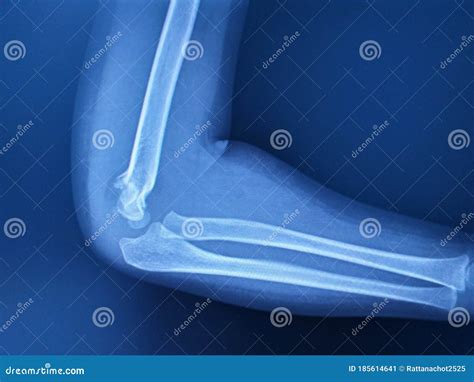

Elbow Joint Effusion occurs when there is an abnormal accumulation of fluid within the joint capsule. The elbow joint is lined with a thin membrane called the synovium, which produces a small amount of fluid to lubricate the cartilage and allow for smooth movement. When the joint is irritated—due to trauma, infection, or chronic inflammatory diseases—the synovium overproduces this fluid, leading to swelling, stiffness, and restricted range of motion.

Because the elbow joint capsule is relatively tight, even a small increase in fluid volume can cause significant pressure. This pressure is often what leads to the sharp pain or aching sensation patients report. It is important to distinguish effusion from bursitis, as the former occurs inside the joint space, whereas bursitis typically occurs in the bursa sac outside the joint.

• Traumatic Injury: Fractures (such as a radial head fracture) or dislocations are the most common causes. The body triggers an inflammatory response to protect the area.

• elbow joint effusion x ray